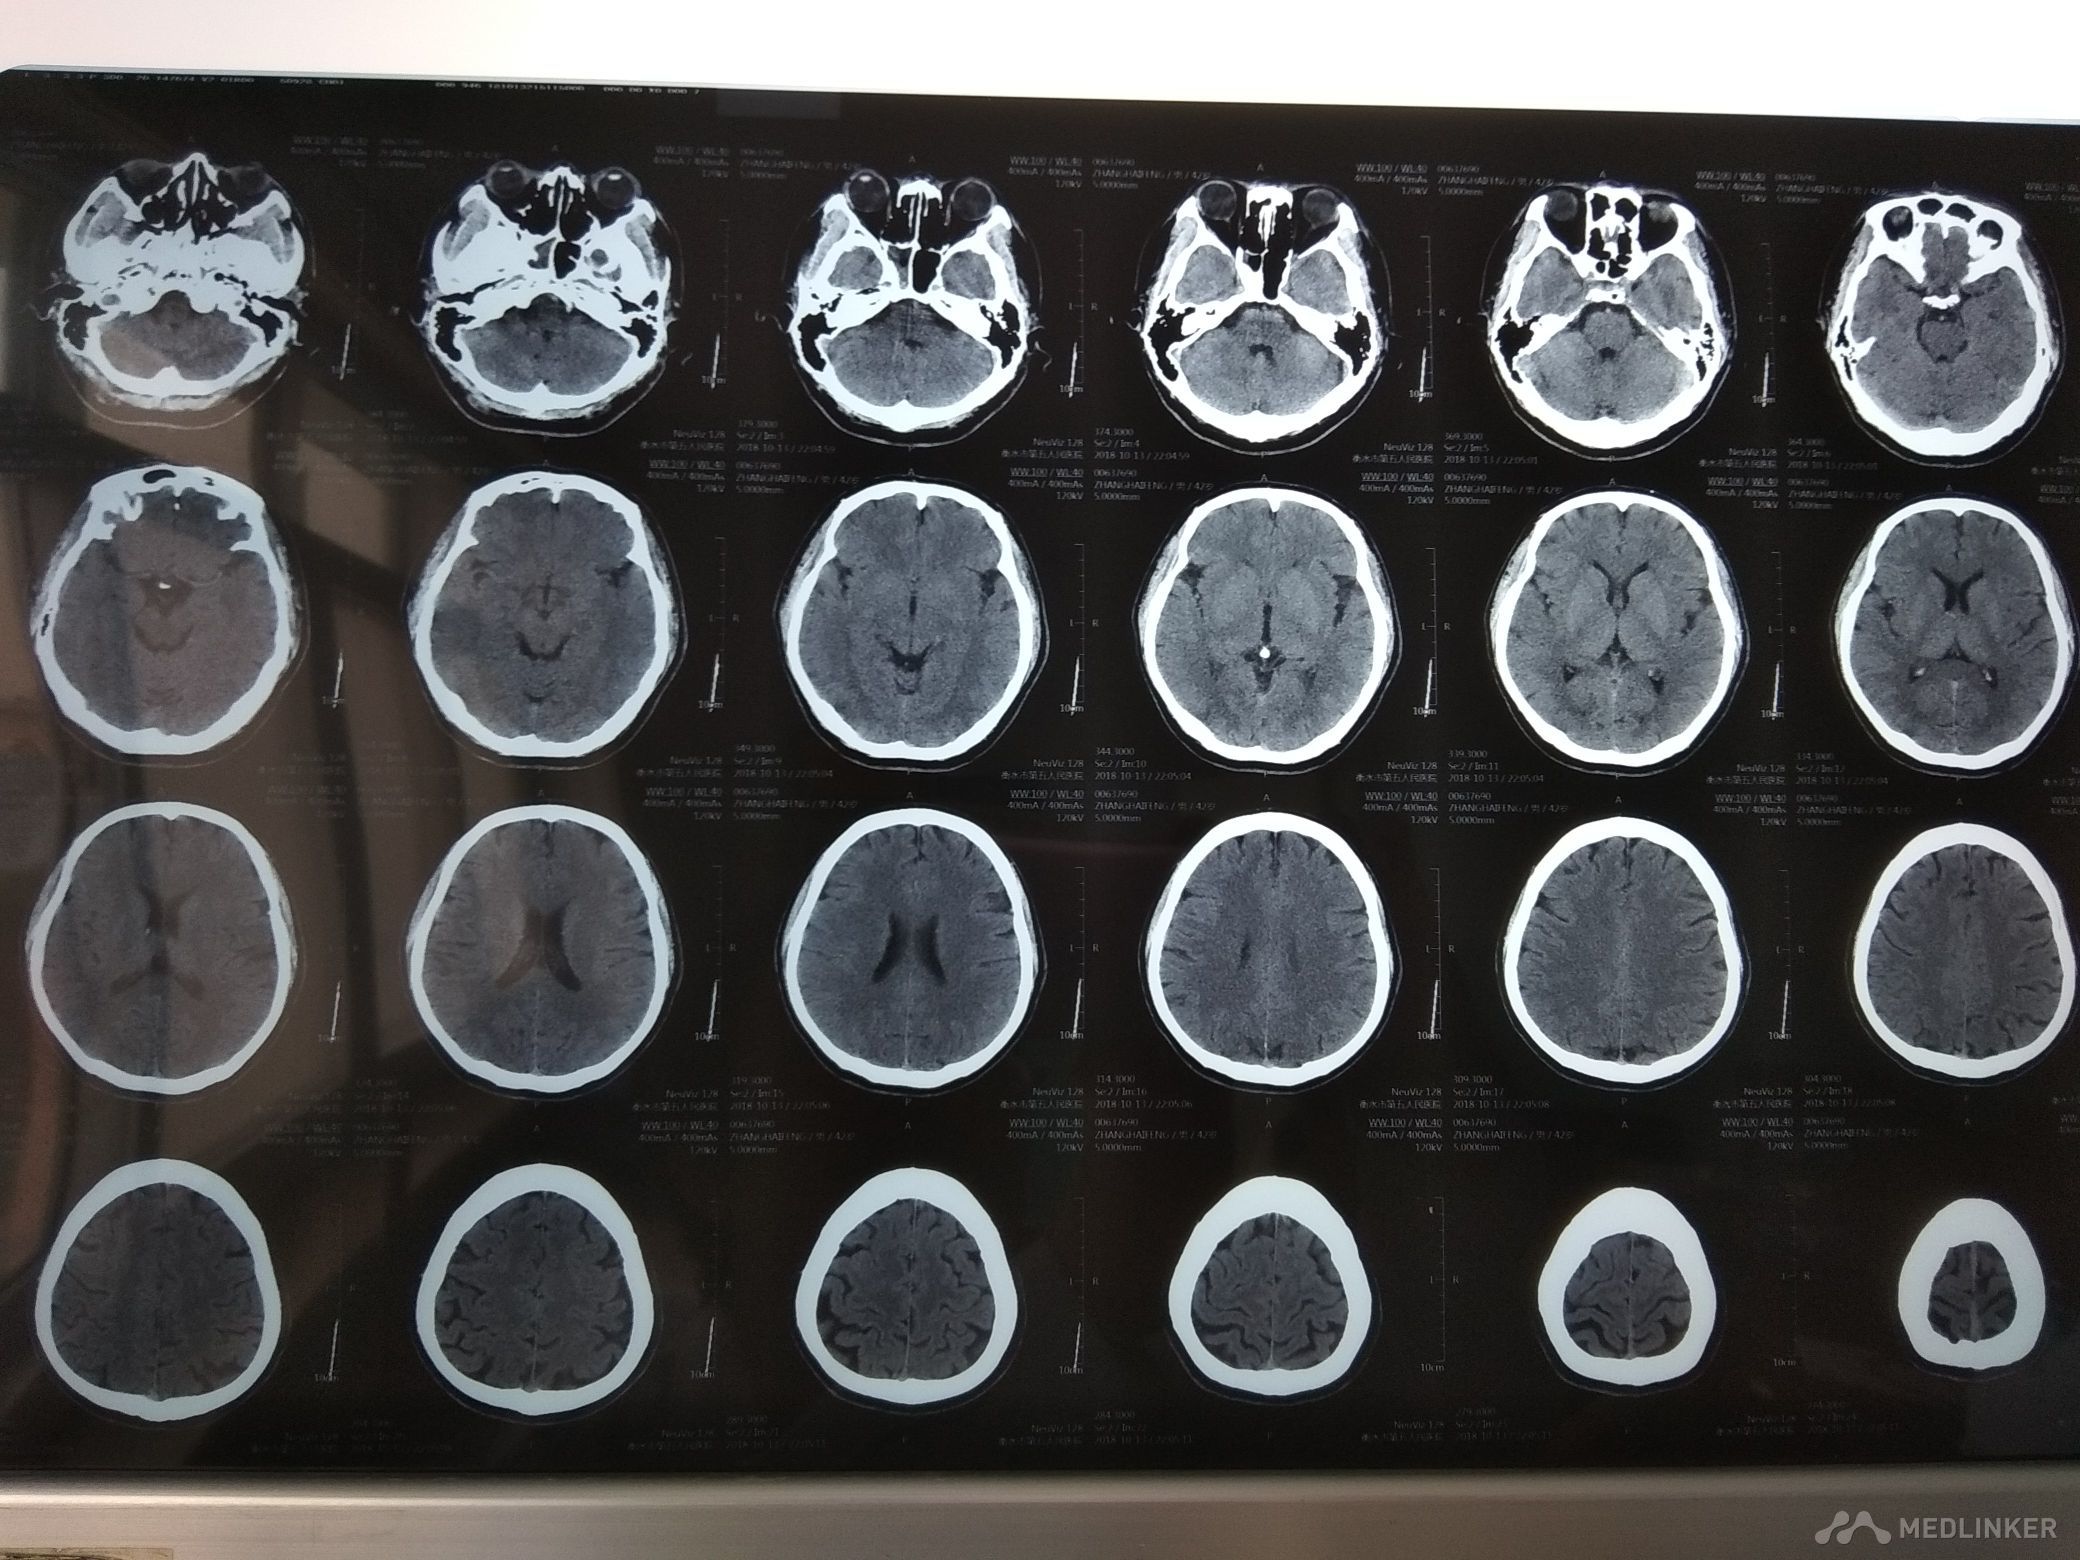

查体BP120/90mmHg,神清,语利,右利手,计算力,记忆力,定向力,理解判断力正常。鼻唇沟基本对称,伸舌稍偏左,四肢肌力5级,肌张力,腱反射适中对称,针刺觉两侧对称,共济检查较稳准,双侧病理征未引出。颈软,双下肢无水肿。肺心腹未见明显异常。 心电图大致正常。头颅MRI颅脑MRA

未见明显异常。 化验结果:血常规,血凝,电解质,肝肾功能,心肌酶,同型半胱氨酸,血脂,血糖正常。